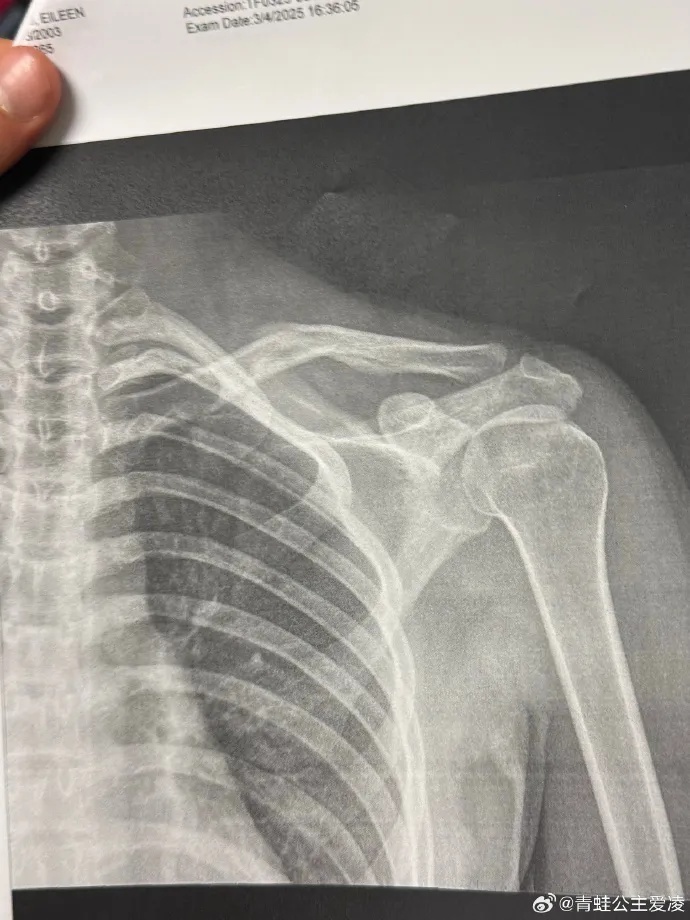

今年3月9日,谷爱凌在社交媒体晒出肩部骨折的X光照片,并配上一个心碎的表情,随后相关话题登上热搜。